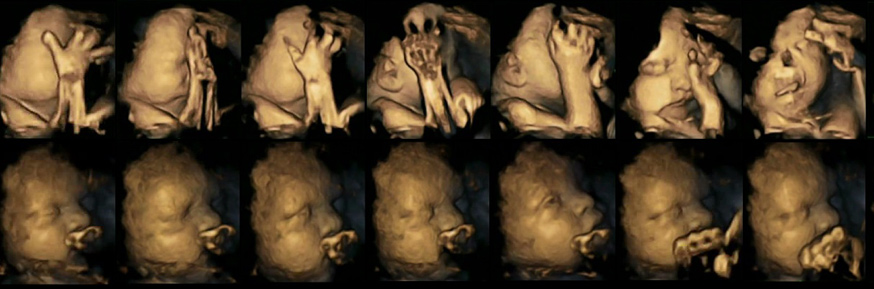

Observing 4-d ultrasound scans, the researchers found that foetuses whose mothers were smokers showed a significantly higher rate of mouth movements than the normal declining rate of movements expected in a foetus during pregnancy.

The researchers observed 80 4-d ultrasound scans of 20 foetuses, to assess subtle mouth and touch movements. Scans were taken at four different intervals between 24 and 36 weeks of pregnancy.

Four of the foetuses belonged to mothers who smoked an average of 14 cigarettes per day, while the remaining 16 foetuses were being carried by mothers who were non-smokers. All foetuses were clinically assessed and were healthy when born.

The study also found some evidence of a bigger delay in the reduction of facial touching by foetuses whose mothers smoked, compared to the foetuses of non-smokers, but the researchers said this delay was less significant.